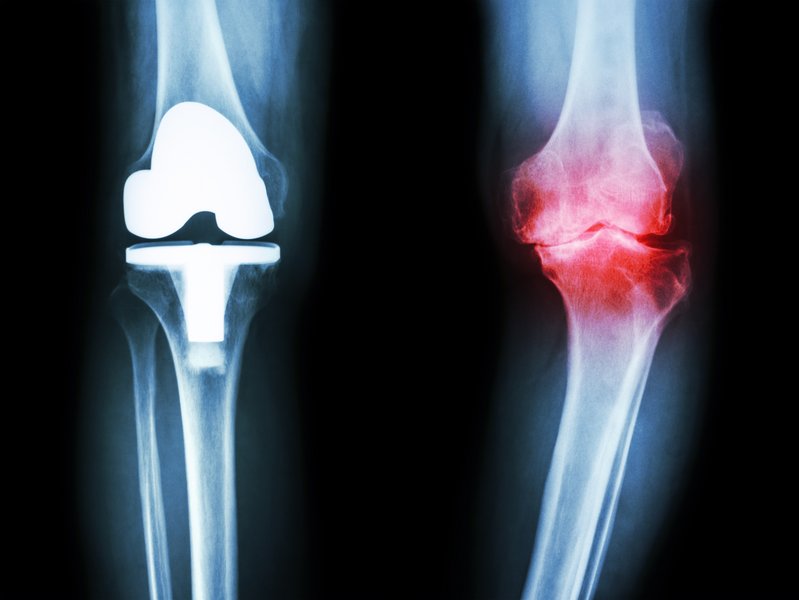

Das umgangssprachliche Wasser im Knie ist ein Anzeichen für eine Erkrankung des Gelenks. Deshalb ist die richtige Diagnose wichtig, um richtig zu behandeln. Flüssigkeit im Knie ist die Folge.. Was ist Arthrose? Symptome, Verlauf und Diagnose im Überblick. Ursachen und Entstehung. Wie entsteht Kniearthrose? Im Laufe des Lebens werden die Knie besonders stark beansprucht. Dabei kann sich der Knorpel im Alter oder bei starker Beanspruchung abnutzen, denn er federt permanent Bewegungen ab und ist der Reibung durch die Knochen ausgesetzt.